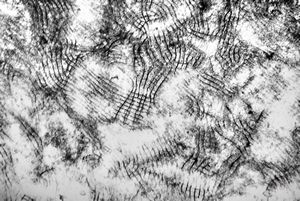

M,50y. | Pneumocystis carinii - lung